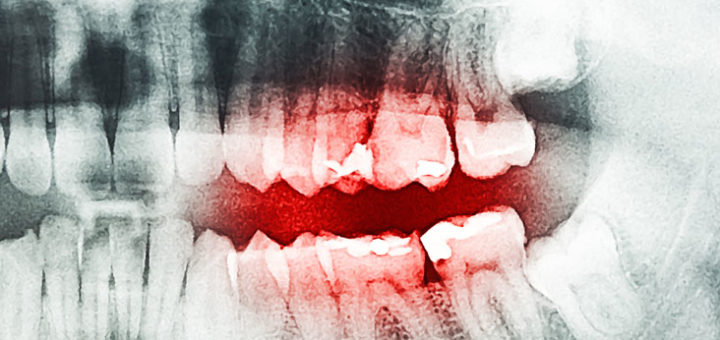

Gum Disease Treatment Gum Disease or Periodontal Disease is an inflammation of the tissues. These tissues support our teeth and help them stay in shape. When a patient suffers from Periodontal Disease the bottom...